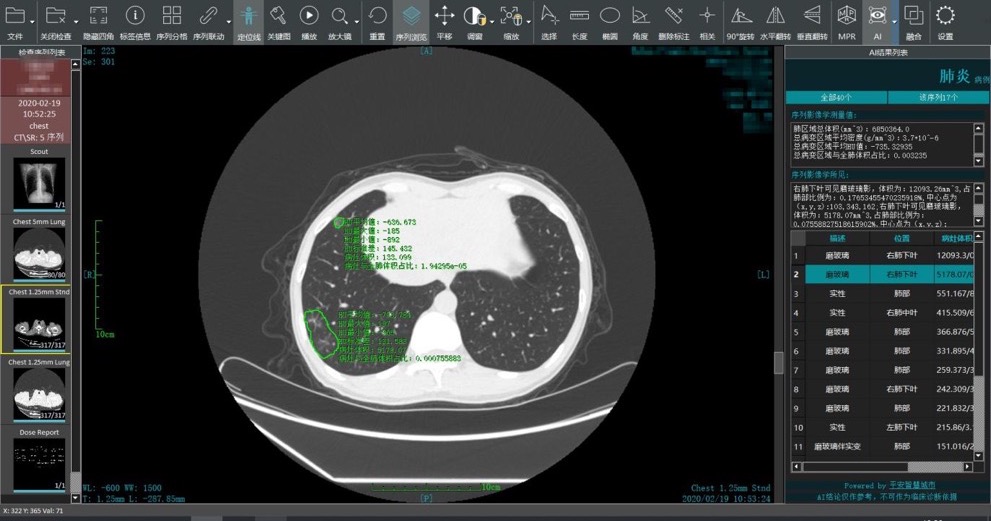

應前線需求,2月19日,平安智慧城市智慧醫療(簡稱:平安智慧醫療)新冠肺炎智能閱片系統正式上線,該系統支持遠程AI讀片和電子膠片影像共享,不僅能在15秒左右出具智能分析結果,而且準確率高達90%,可以幫助放射科醫生精準識別病灶、在更短的時間內快速出具診斷報告、同時具備電子膠片影像共享功能,減少重複拍片,可以輔助醫生儘早發現、快速報告、精準診斷。

平安智慧醫療發揮人工智能科技優勢開發的新冠肺炎智能閱片系統,通過人工智能分析引擎,對新冠肺炎CT影像進行智能化分析與定量評價,並對同一患者不同次掃描圖像進行對比分析,定量測量病灶的改變情況,輔助醫生對患者的病情發展趨勢、治療效果、轉歸情況等進行智能評估,幫助醫生快速、有效的完成對新冠肺炎患者的檢出、分診和評估,輔助醫護人員打贏防「疫」戰。

為此,平安智慧醫療在利用臨床診斷數據充分訓練AI模型後,推出的「新冠肺炎智能閱片」 CT+AI的輔助診斷系統派上了用場,通過智能識別磨玻璃影、肺實變和混合磨玻璃影等功能,幫助醫生更為快速和準確識別病灶。並且,該系統背後依託的平安智慧醫療智能影像技術歷年來在多個國際醫療影像挑戰賽中碩果累累,比如2019年就在國際頂級醫療影像會議ISBI競賽中獲得肺癌病理分割總冠軍、內鏡影像質控總冠軍等成績。